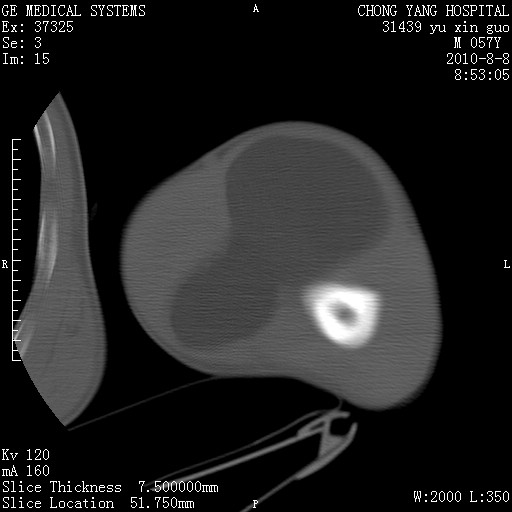

标题: CT28267:M57Y 上臂包块8年余。 [打印本页]

标题: CT28267:M57Y 上臂包块8年余。

包膜光滑、完整的脂肪密度肿块,支持脂肪瘤。